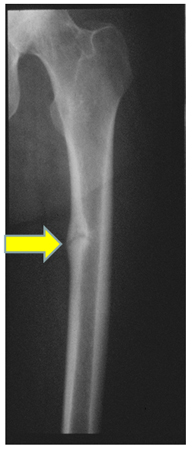

Osteomalácia

Radiografia da haste femoral em paciente com osteomalácia demonstrando "pseudofratura" (também conhecida como zona de Looser) no aspecto medial da haste femoral média

Do acervo de Bridget Sinnott, MD; usado com permissão